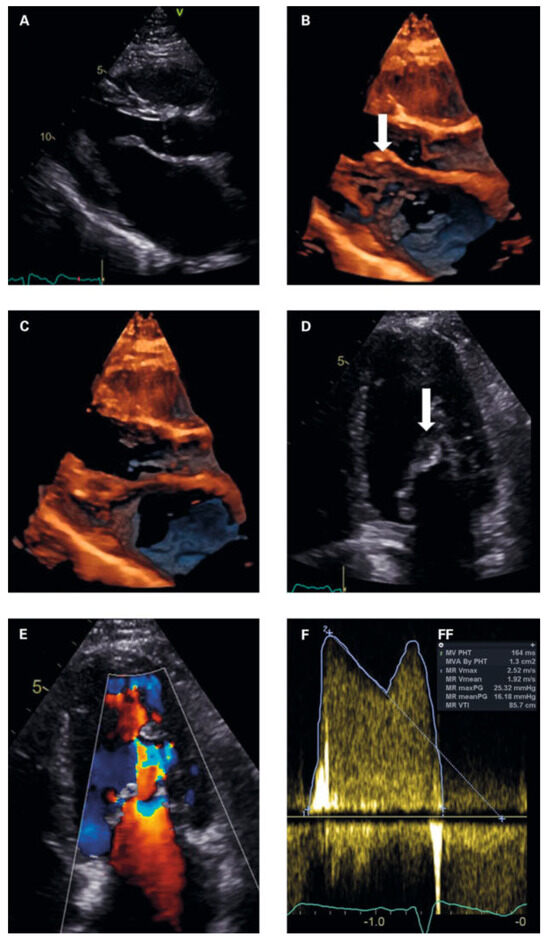

Occasionally, cardiac disease may manifest acutely with extracardiac symptoms. We present a patient case with pulmonary haemorrhage as the first manifestation of rheumatic mitral stenosis, which resolved completely after mitral valve surgery, and discuss the pathophysiology and clinical management of this rare manifestation [...] Read more.

Occasionally, cardiac disease may manifest acutely with extracardiac symptoms. We present a patient case with pulmonary haemorrhage as the first manifestation of rheumatic mitral stenosis, which resolved completely after mitral valve surgery, and discuss the pathophysiology and clinical management of this rare manifestation of rheumatic heart disease. Full article